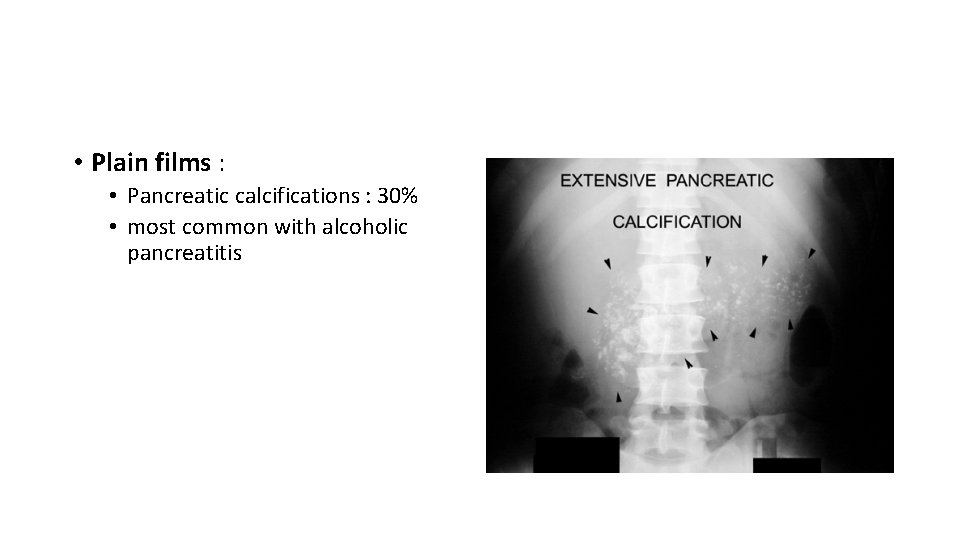

• Plain films : • Pancreatic calcifications : 30% • most common with alcoholic pancreatitis

Pancreatic calcifications. CT scan showing multiple, calcified, intraductal stones in a patient with hereditary chronic pancreatitis Endoscopic retrograde cholangiopancreatography in chronic pancreatitis. The pancreatic duct and its side branches are irregularly dilated 55